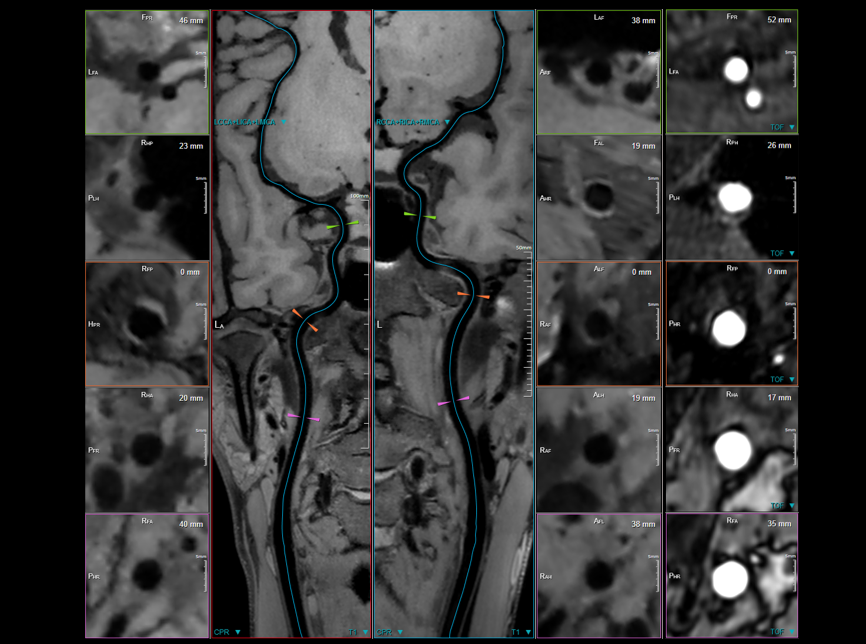

“静音”血管成像

高分辨血管壁成像